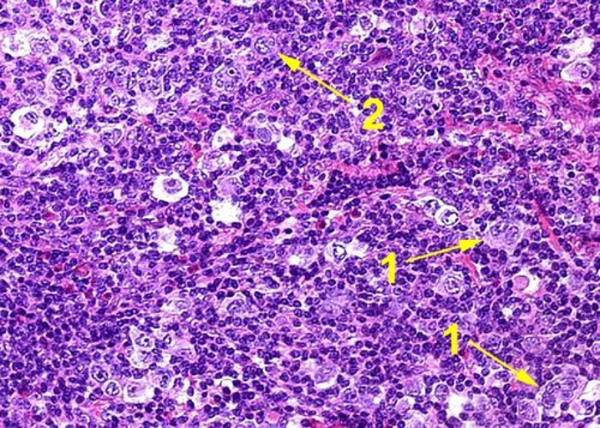

Микропрепараты: Лимфогранулематоз и Нодулярный Склероз

Раздел: Секреты мастерства